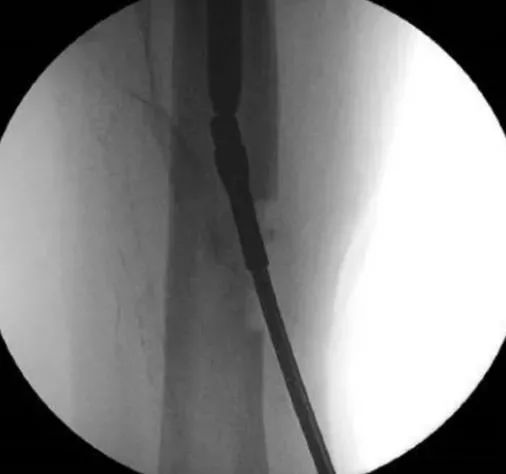

Введение тонкого интрамедуллярного стержня или ручного римера в дистальный отдел сломанного гвоздя также иногда помогает удалить его.Во время забивания дистальный стопорный штифт следует удерживать, чтобы избежать дальнейшего смещения дистальной части во время забивания.После того, как тонкий интрамедуллярный стержень или ручная фреза прочно вошли в дистальный сегмент, удалите дистальный блокирующий стержень, а затем ударьте по нему, чтобы удалить сломанный дистальный сегмент.

Наконец, если все вышеперечисленные методы проксимального удаления не дали результата, можно попытаться удалить интрамедуллярный стержень дистально.Например, сломанную дистальную часть бедренного интрамедуллярного стержня удаляют через отверстие в дистальном отделе бедренной кости через коленный сустав.Сверло ориентировано на дистальный конец интрамедуллярного стержня, а отверстие достаточно велико, чтобы в него можно было вставить проводник с оливковым наконечником и прокладкой.Проводник ретроградно проводится через полость интрамедуллярного стержня и выступает из отверстия проксимального отдела бедренной кости, а головка оливы со спейсером может вывести дистальный сломанный стержень из проксимального отдела бедренной кости.Аналогичная техника может быть использована для большеберцовой кости с ретроградным введением дистального отверстия проводника в медиальной лодыжке.Иногда через отверстие вводят спицу Штейнера и ударяют по сломанному ногтю на дистальном конце, чтобы сломанный ноготь мог немного сместиться проксимально, что полезно для ретроградного введения иглы-проводника и удаления сломанного ногтя.